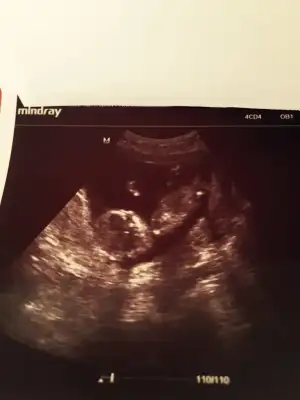

Kızlar sizce cinsiyeti ne bilenler söyleyebilir mi

BENCE ERKEK :)Kızlar sizce cinsiyeti ne bilenler söyleyebilir mi

yorum yapan arkadaşlara tşk ederim :)%90 erkek dedi dr :)[/QUO